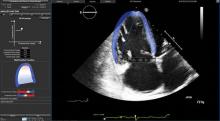

September 7, 2016 — Toshiba America Medical Systems Inc. announced that its Aplio 500 Platinum ultrasound system will be used during a live case following the International Contrast Ultrasound Society (ICUS) Bubbles Conference, Sept. 8-9 in Chicago. The demonstration is meant to show the benefits of the recent U.S.